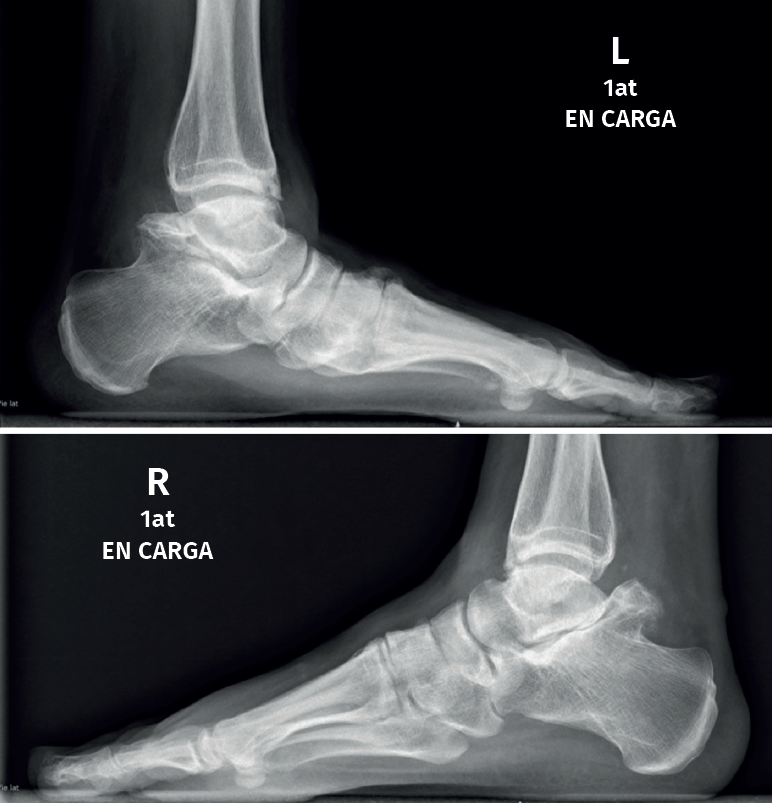

El os trigonum se presenta habitualmente de forma bilateral; puede alcanzar hasta 1,5 cm de diámetro (Figura 2) y presentarse dividido en 2 (os trigonum bipartitum). Cuando se fusiona al astrágalo se le denomina proceso trigonal y no es rara su presentación como os trigonum en un lado y proceso trigonal en el otro(4).

A lo largo de muchos años de trabajo, nuestra unidad ha reunido un número notable de casos con un cuadro clínico muy característico. Son pacientes adultos de ambos sexos con dolor en la parte posterior de la articulación subastragalina, pero también en la cara anterior del tobillo, a veces de forma bilateral, y que presentan un aspecto radiológico complejo con masas óseas posteriores muy separadas del astrágalo, basculación hacia atrás de este, artrosis subastragalina y choque tibioastragalino anterior con formación de osteofitos.